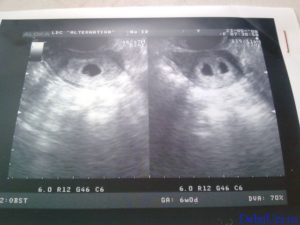

Единственный надежный способ подтвердить беременность двойней – это ультразвуковое исследование. Поэтому многие женщины не знают об этом до первого ультразвукового сканирования через 10-13 недель после зачатия. Однако следует учесть, если плодов больше двух, становится сложнее точно определить их количество.

В случаях осложнений беременности, таких как кровотечение, или после лечения бесплодия, первое ультразвуковое исследование будет, скорее всего, через 6 недель. Однако на данном этапе трудно заметить два плода. Изредка бывает, что при зачатии у женщины наступает беременность двойней, но в дальнейшем развивается только один плод. Это известно как синдром «исчезающего близнеца».

Ультразвуковое исследование Этот метод позволяет увидеть близнецов в матке беременной женщины. Если есть подозрение, что у вас больше одного ребёнка, лучше сказать об этом своему врачу, чтобы он лучше смотрел. Хотя маловероятно, что УЗИ может пропустить второй плод. Однако бывают ошибки при подсчёте в случае более многоплодной беременности или в случае скрытого близнеца.